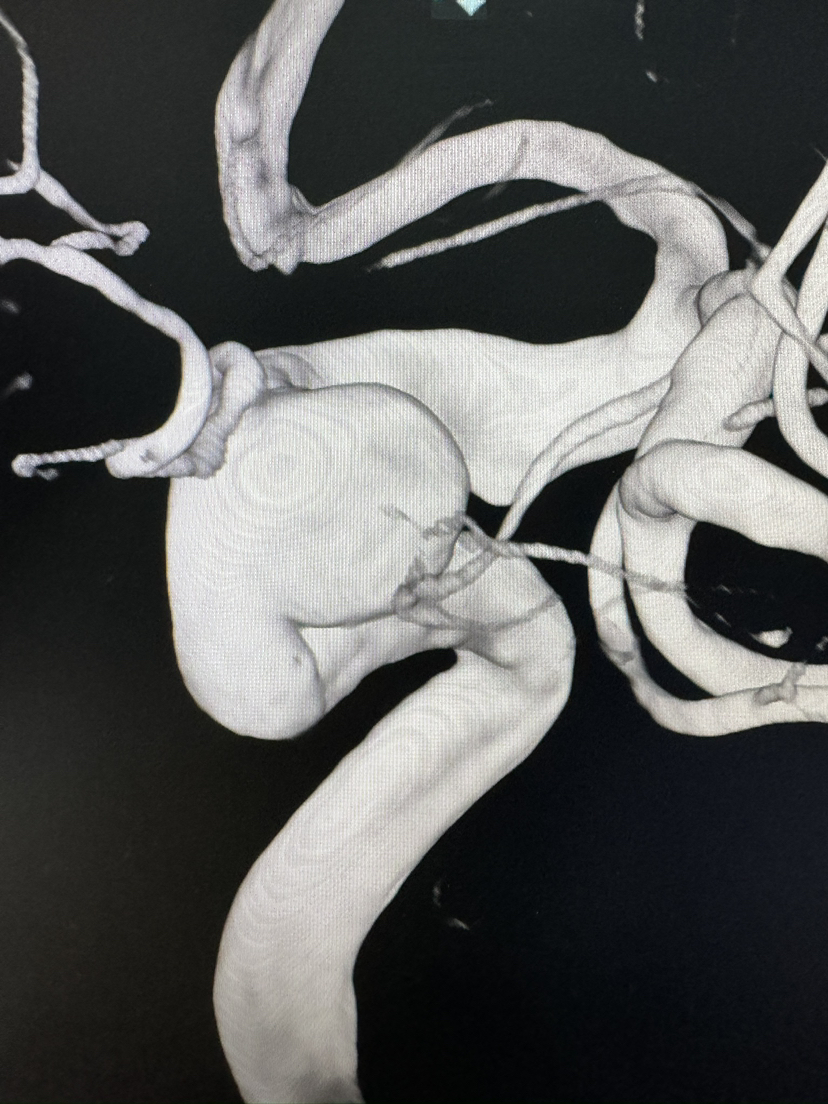

Lattice 支架治疗眼动脉动脉瘤,Scepter c 球囊后扩辅助海绵窦段支架打开